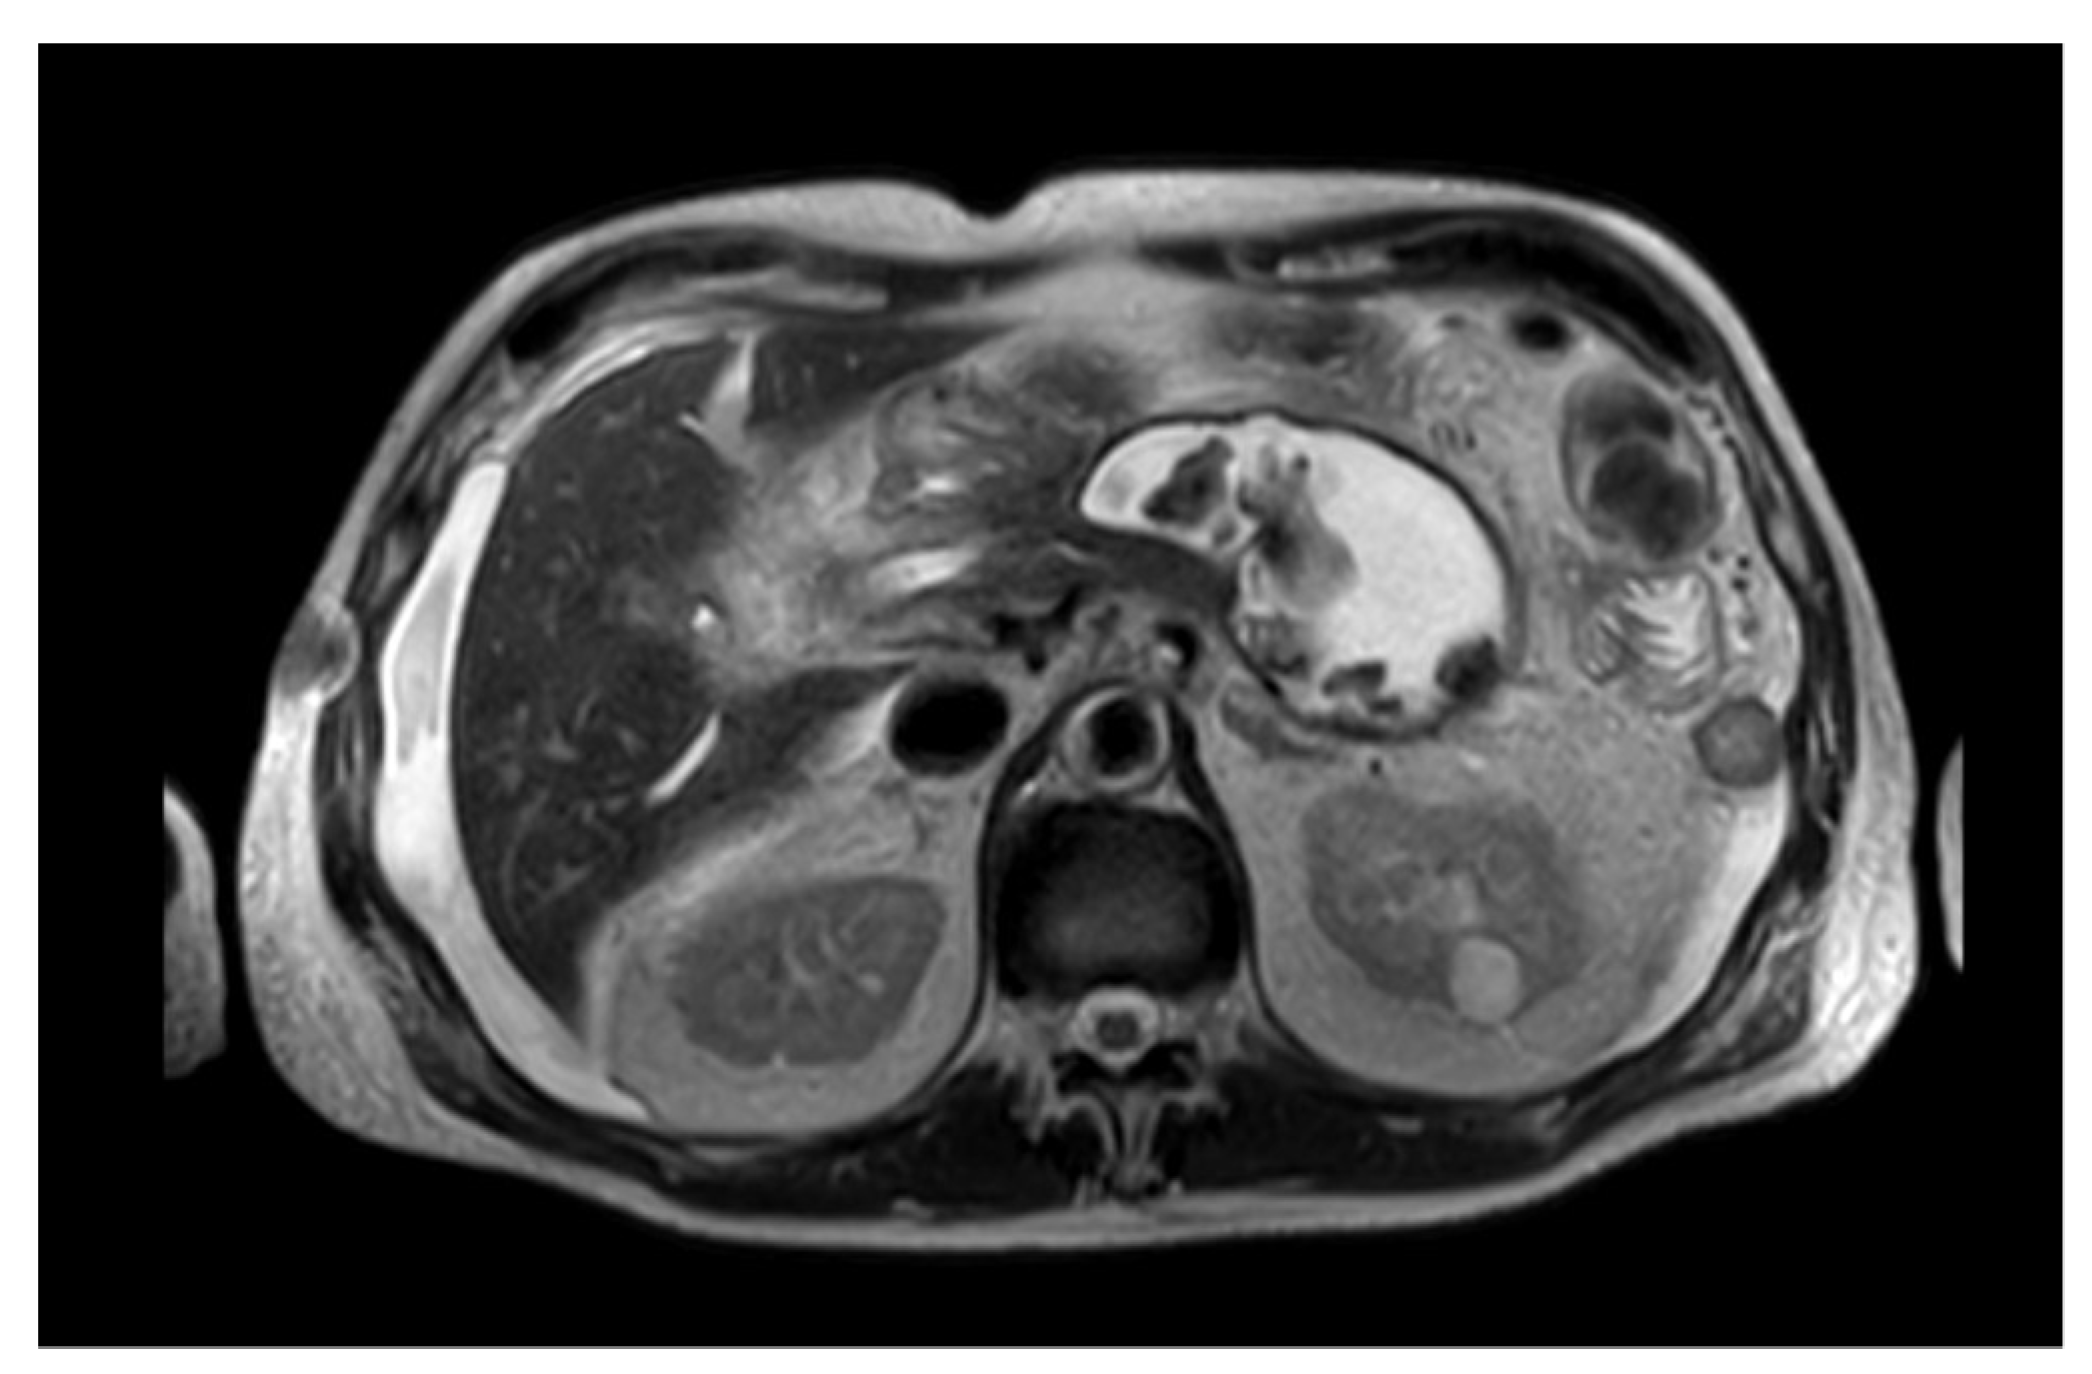

- EC-LAMS: the deployment catheter is positioned on the selected point on the gastric/duodenal wall. The activation of the electro-cautery tip allows direct passage of the catheter into the collection under EUS guidance. The distal flange of the LAMS is deployed, and the next steps are the same as the LAMS (Figure 3) [50].